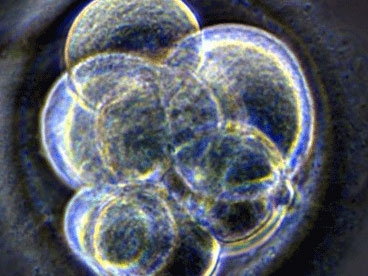

——重建原始生殖细胞多样性来源:汉氏联合胎盘干细胞哺乳类原始生殖细胞(PGCs)是配子的单能性前体细胞。但是PGCs能够在体外直接产生多能干细胞,或者在畸胎癌发生过程中产生多能细胞。这种转变并无规律,难以研究。剑桥大学的科研人员明确在培养过程中有效重建多能